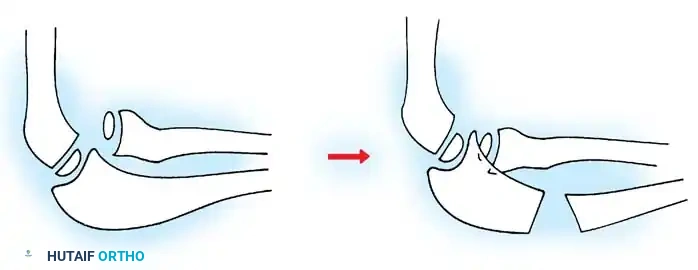

Fig. 33-39 A, Fracture occurring when elbow dislocation is reduced. B, Fractures occurring at time of elbow dislocation.

Fractures can present as angulated, translocated (shifted), or totally displaced. In the context of an elbow dislocation, the proximal fragment may become loose within the joint space or trapped, acting as a mechanical block to reduction.